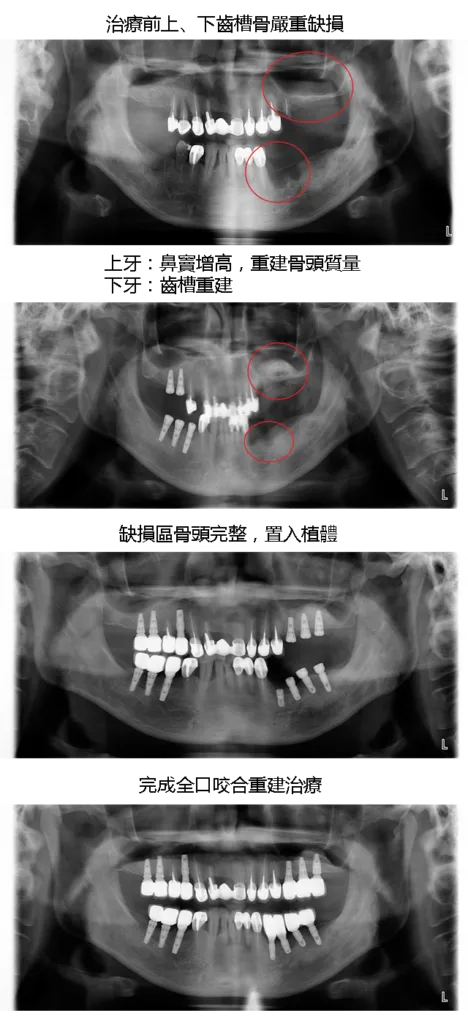

[ 湯先生植牙案例 ]